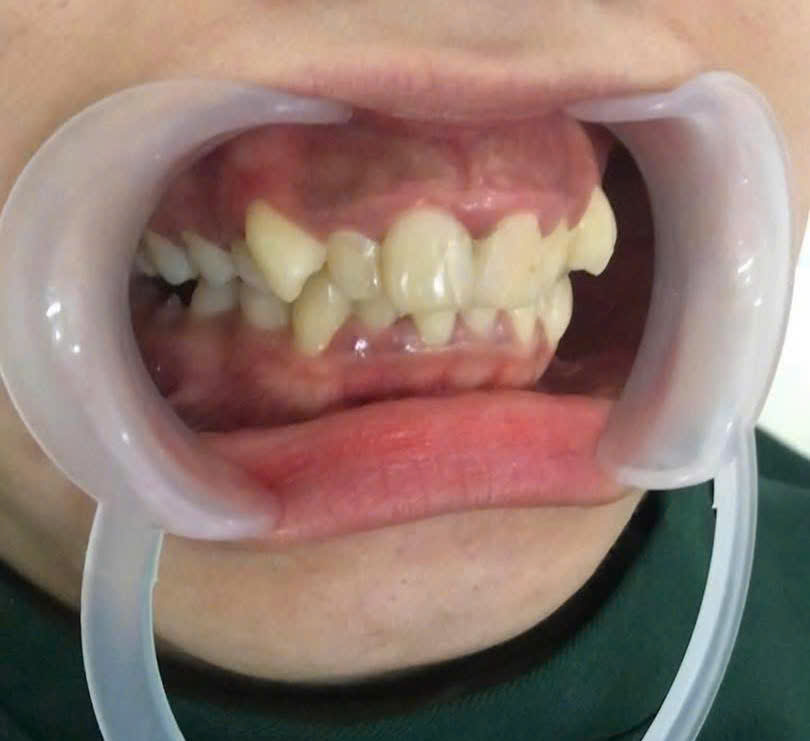

Nụ cười không chỉ là “ngôn ngữ chung của hạnh phúc”, mà còn là yếu tố quyết định sự tự tin trong giao tiếp, học tập và công việc. Tuy nhiên, không ít khách hàng gặp tình trạng cười hở lợi, thân răng ngắn, viền lợi không đều hoặc xương ổ phát triển quá mức khiến gương mặt mất cân đối.

Đó cũng là lý do mà khách hàng từ Cambodia đã không ngần ngại vượt hàng trăm km sang Việt Nam, tìm đến Nha Khoa Ân Đức Luxury để được bác sĩ Tài trực tiếp thăm khám và thực hiện cắt lợi làm dài thân răng kết hợp mài xương ổ.

⇒ Kết quả sau ca tiểu phẫu: một nụ cười hài hòa, tự nhiên, cân xứng, đồng thời đảm bảo sức khỏe răng miệng lâu dài.